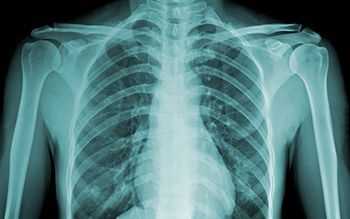

Как правило, в диагностических целях проводят рентгенографию грудной клетки, но может потребоваться целенаправленная визуализация плоской грудной кости посередине ее передней стенки - рентген грудины.

Что показывает рентген грудины? На рентгеновском снимке грудина (sternum) - начинающаяся ниже яремной выемки рукоятка (manubrium sterni), тело (corpus sterni) и мечевидный отросток (processus xiphoideus) - видна вдоль позвоночника без наложения позвонков, также над тенью сердца просматриваются кортикальные контуры кости; визуализируются и грудино-ключичные суставы (articulatio sternoclavicularis).

По стандарту, делают рентген грудины в 2 проекциях: в латеральной (боковой) и передней косой.

Рентген грудины в боковой проекции - наиболее информативный в случаях перелома грудины и определения степени смещения, а также выявления метастазов - проводится в вертикальном положении пациента (сидя или стоя). При этом одна из сторон грудной клетки пациента должна прилегать к рентгеновской кассете, его руки заводятся за спину, отводя плечи кзади (чтобы грудная клетка выдвигалась вперед), а подбородок приподнимается. По команде техника-рентгенолог пациенту нужно на несколько секунд затаить дыхание.

Часто боковую проекцию дополняет правая передняя косая проекция, при которой пациент наклоняется вперед на 15-25°, а центральный луч направляется перпендикулярно пленке - чуть левее позвоночного столба, посередине между яремной выемкой и мечевидным отростком. При наличии тяжелой травмы рентген проводится лежа - в левой задней косой проекции.

Рентген-признаки перелома грудины

Рентгенограммы грудной клетки обычно являются первичной визуализацией у пациентов с подозрением на травмы грудины. Было показано, что переднезадняя рентгенограмма имеет только 50% чувствительность для выявления переломов грудины. Боковой рентгенологический снимок увеличивает чувствительность и обычно является диагностическим, так как большинство переломов грудины являются поперечными, и любое смещение происходит в сагиттальной плоскости.

И их рентген-признак - появление темных промежутков на светлом фоне плоской грудной кости, что является отображением линий переломов. Убедительным подтверждением перелома является видимое на снимке смещение отломков. [2]